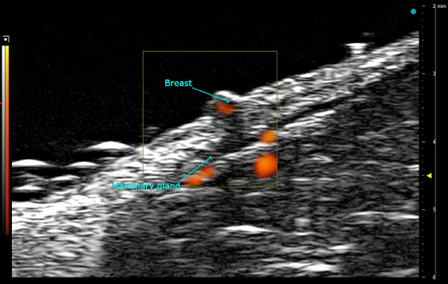

Custom services General Sonography

Beyond specialized applications, we offer ultrasound-based assessment of multiple organs in rodent models, with options for structural and functional analysis:

- Reproductive organs – Imaging of uterus, testes, and mammary glands for developmental or pathological studies.